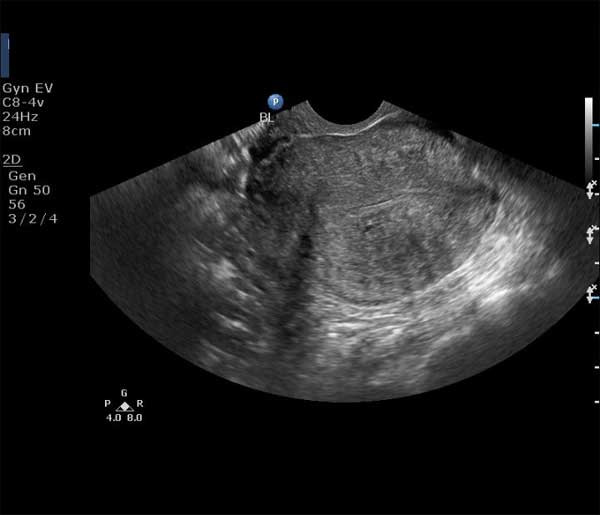

This middle-aged woman has pelvic pain and vaginal discharge. What is your diagnosis based on these ultrasound images of the uterus?

There is a clearly defined rounded mass just below the endometrial stripe of the uterus. The endometrium itself appears normal in thickness ruling out hyperplasia.The mass is within the uterine fundus and body ruling out a cervical mass.